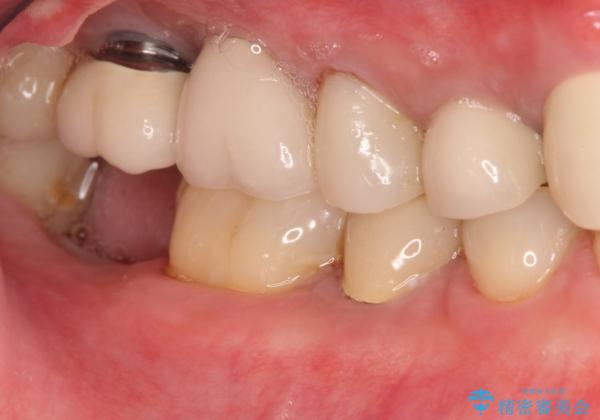

右下の奥歯を抜歯 インプラント治療による咬合回復

- 右下の奥歯をかぶせ物がとれたまま放置しているところに歯を入れたいとのことで来院されました。

精査すると保存が難しいため抜歯をして、インプラントを埋入、かぶせ物を装着する計画としました。

インプラント治療により、周りの歯を削ることなく咬合を回復することができました。